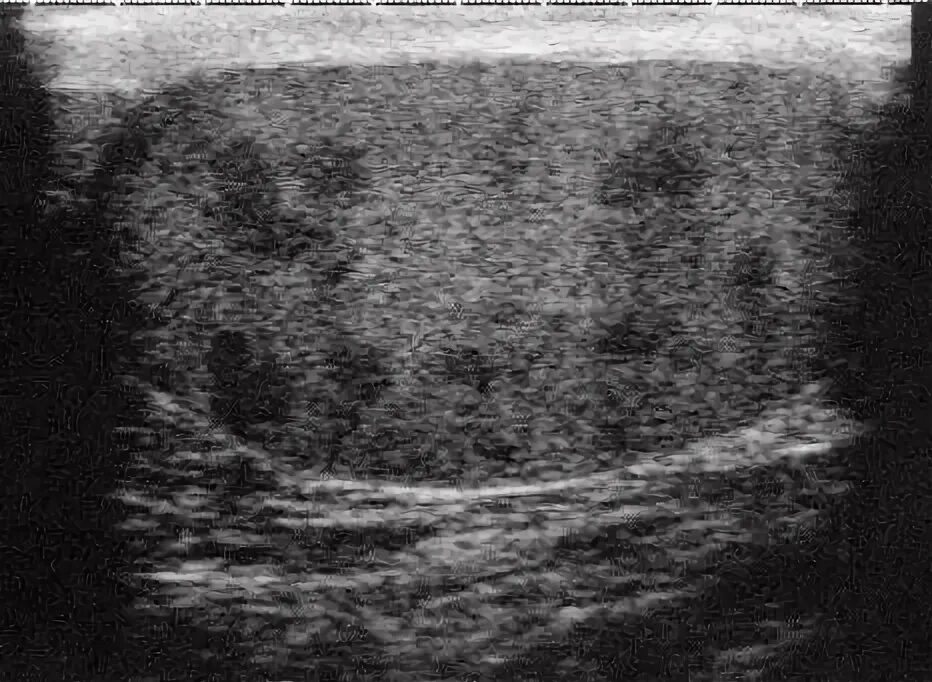

Белое пятно на узи